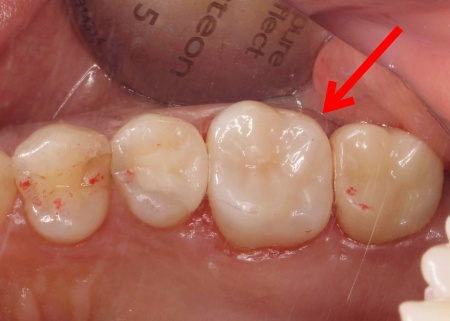

50代女性銀歯の下の虫歯を除去しセラミックで修復したケース

レントゲン像で金属の下に虫歯があり、患者さんは入れ替えを強く希望されました。

特に審美的な要求をされたため、セラミック修復の説明をし、治療の同意を得ました。